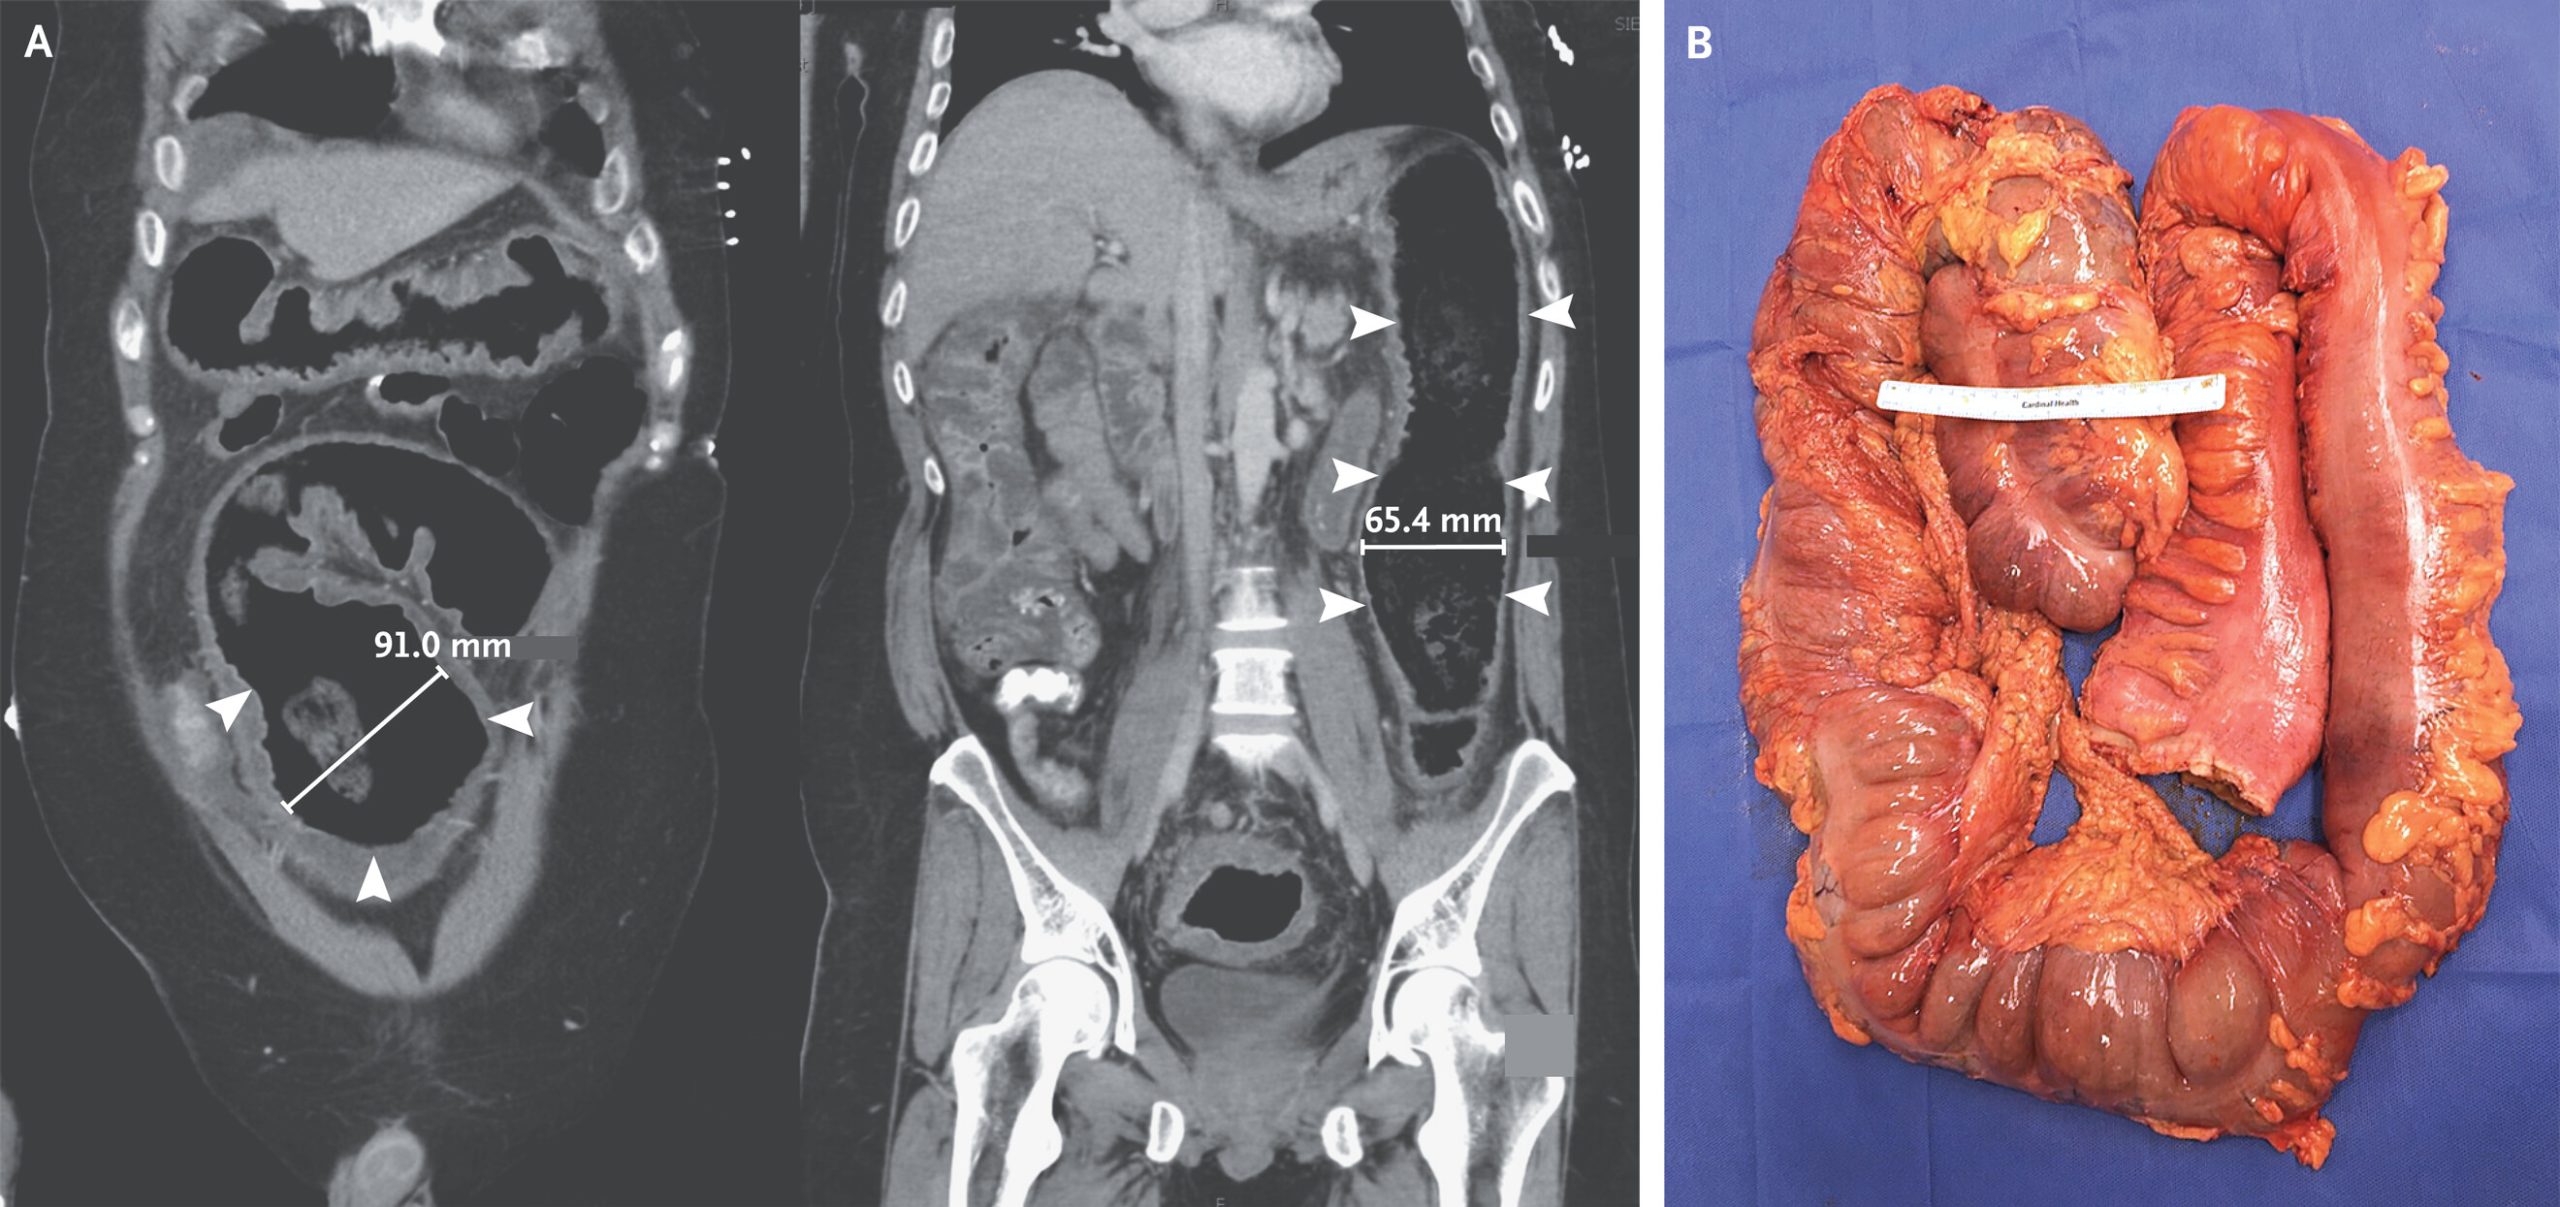

Secara klinis, megakolon toksik didefinisikan sebagai pelebaran kolon non-obstruktif dengan diameter lebih dari 6 sentimeter yang disertai toksisitas sistemik. Furthermore, kondisi ini berbeda dari megakolon biasa karena melibatkan kerusakan parah pada lapisan dinding usus besar. Ketika peradangan sudah menembus seluruh lapisan dinding kolon, fungsi motorik usus akan terganggu total.

- CT scan abdomen yang memberikan gambaran lebih detail tentang kondisi usus besar

Additionally, jika terapi konservatif tidak menunjukkan perbaikan dalam waktu 24 hingga 72 jam, dokter akan mempertimbangkan tindakan pembedahan. Prosedur kolektomi atau pengangkatan sebagian maupun seluruh usus besar menjadi pilihan utama untuk mencegah komplikasi yang lebih fatal. Dalam beberapa kasus, dokter juga perlu melakukan perbaikan pada bagian usus yang mengalami perforasi agar bakteri tidak menyebar ke rongga perut.